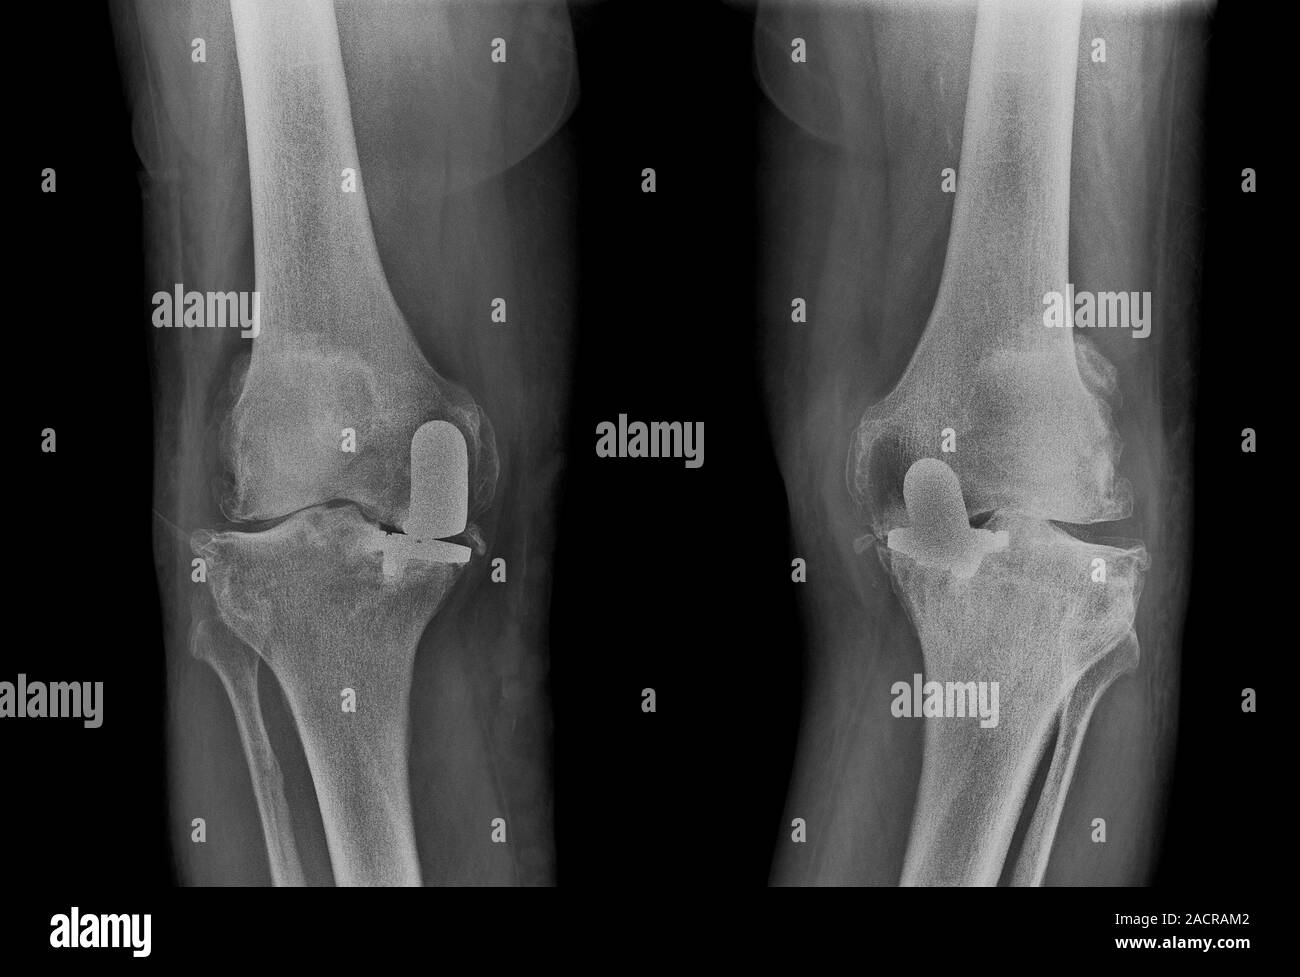

From es.dreamstime.com

Artritis De La Rodilla De La Radiografía Imagen de archivo Imagen de Que Causa La Artritis En Las Rodillas esta forma más común de artritis afecta principalmente a las articulaciones de las manos, las rodillas, las caderas y la columna vertebral. La artritis de rodilla, también conocida como osteoartritis de rodilla, es una enfermedad degenerativa. la enfermedad suele afectar las manos, las rodillas y los tobillos, y generalmente la misma articulación en ambos lados del. la. Que Causa La Artritis En Las Rodillas.

From www.alamy.es

La artritis en las rodillas. Radiografía de la rodilla de un paciente Que Causa La Artritis En Las Rodillas si experimenta dolor, hinchazón y rigidez en las rodillas, es posible que tenga uno de los siguientes tipos de artritis o afecciones. esta forma más común de artritis afecta principalmente a las articulaciones de las manos, las rodillas, las caderas y la columna vertebral. La artritis de rodilla, también conocida como osteoartritis de rodilla, es una enfermedad degenerativa.. Que Causa La Artritis En Las Rodillas.